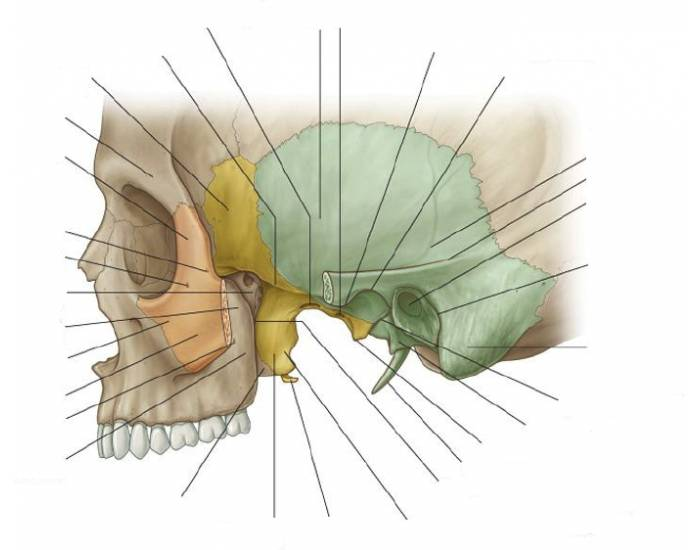

Анатомические особенности: фотографии ямок черепа, височной и подвисочной крылонебной